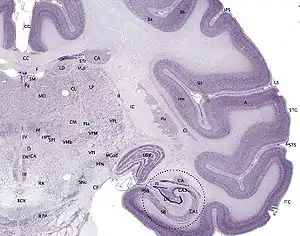

The cerebral cortex, also known as the cerebral mantle,[1] is the outer layer of neural tissue of the cerebrum of the brain in humans and other mammals. The cerebral cortex mostly consists of the six-layered neocortex, with just 10% consisting of the allocortex.[2] It is separated into two cortices, by the longitudinal fissure that divides the cerebrum into the left and right cerebral hemispheres. The two hemispheres are joined beneath the cortex by the corpus callosum. The cerebral cortex is the largest site of neural integration in the central nervous system.[3] It plays a key role in attention, perception, awareness, thought, memory, language, and consciousness. The cerebral cortex is part of the brain responsible for cognition.

A fold or ridge in the cortex is termed a gyrus (plural gyri) and a groove is termed a sulcus (plural sulci). These surface convolutions appear during fetal development and continue to mature after birth through the process of gyrification. In the human brain the majority of the cerebral cortex is not visible from the outside, but buried in the sulci.[7] The major sulci and gyri mark the divisions of the cerebrum into the lobes of the brain. The four major lobes are the frontal, parietal, occipital and temporal lobes. Other lobes are the limbic lobe, and the insular cortex often referred to as the insular lobe.

The cerebral cortex is the outer covering of the surfaces of the cerebral hemispheres and is folded into peaks called gyri, and grooves called sulci. In the human brain it is between 2 and 3-4 mm. thick,[8] and makes up 40% of the brain's mass.[3] 90% of the cerebral cortex is the six-layered neocortex whilst the other 10% made up of three/four-layered allocortex.[3] There are between 14 and 16 billion neurons in the cortex,[3] and these are organized radially in cortical columns, and minicolumns, in the horizontally organized layers of the cortex.[9][10]

The neocortex is separable into different regions of cortex known in the plural as cortices, and include the motor cortex and visual cortex. About two thirds of the cortical surface is buried in the sulci and the insular cortex is completely hidden. The cortex is thickest over the top of a gyrus and thinnest at the bottom of a sulcus.[11]